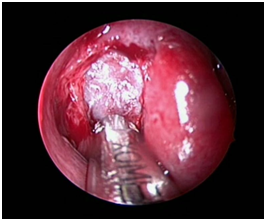

A 22years old male presented with bilateral blocked nose sensation (right>left) since 7-8months, persistent frontal headache. History of right sided facial heaviness and pain with right periorbital swelling. No history of trauma, clear fluid discharge from nose. No history of recurrent episodes of upper respiratory tract infections/ recurrent episodes of sneezing/running nose or any previous trauma. On examination, anterior rhinoscopy showed mucopurulent discharge and crusting, nasal endoscopy showed bilateral inferior turbinate hypertrophy, mucosa was normal. CT scans of paranasal sinuses showed large homogenous expansile cystic lesion obstructing the right frontal sinus drainage. Another homogenous mass was noted in extending to the right ethmoid sinus suggesting the possible diagnosis of two separate frontal and ethmoid mucoceles with pansinusitis and right sided proptosis (Figure 1-3).

Figure 1 & 2 CT scans showing homogenous masses in the right frontal and ethmoid sinuses.

Figure 3 CT scan suggestive of right side proptosis.